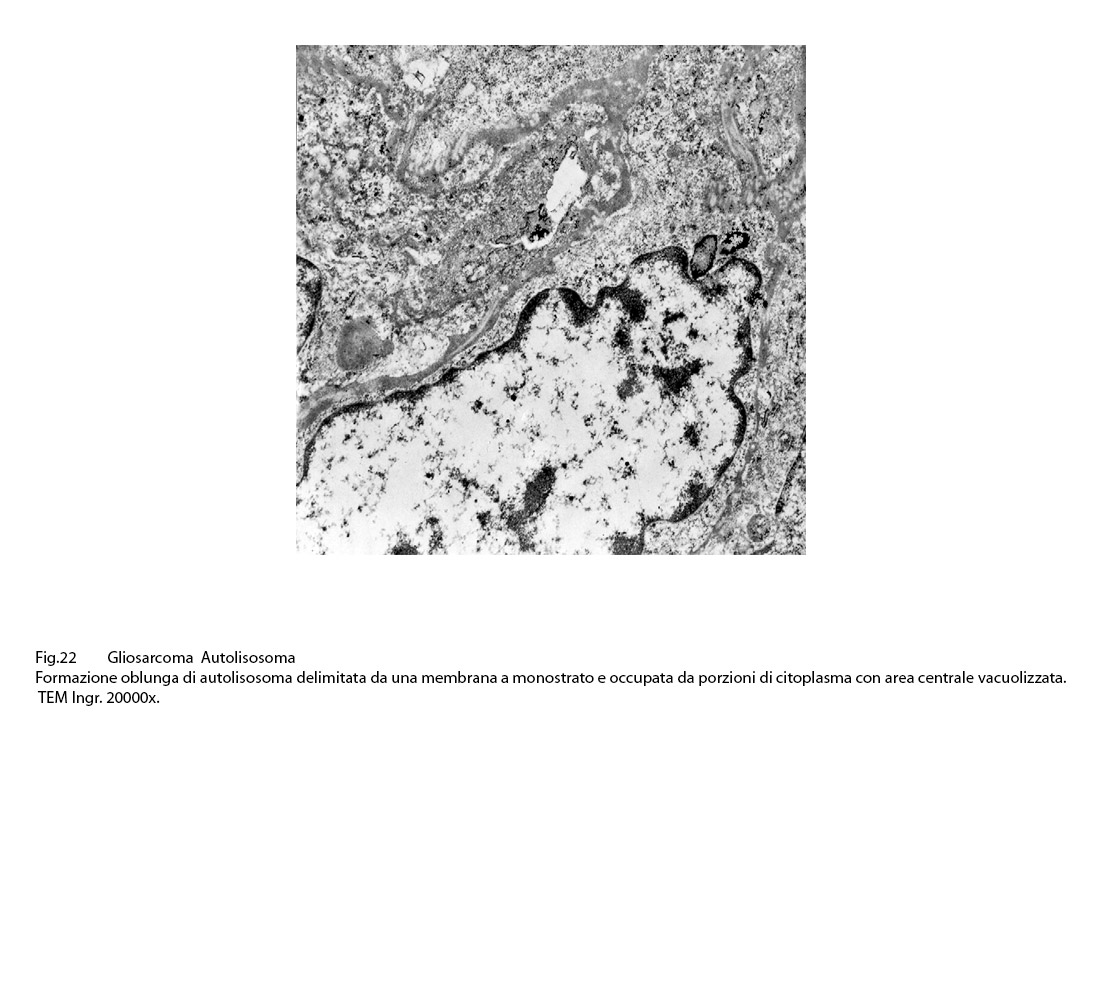

AUTOFAGOSOMI E AUTOLISOSOMI

L’autofagosoma è un focolaio vescicoloso endocellulare,di diverse dimensioni,di forma sferoidale,delimitato da una membrana a doppio strato;al suo interno si ritrovano materiali biologici eterogenei di aspetto granuloso,filamentoso,amorfo,tubulare e nei focolai voluminosi anche organelli citoplasmatici o frammenti nucleari.

Dopo questa fase di accumulo del cargo,segue quella della fusione tra l’autofagosoma e un lisosoma con formazione di una nuova struttura indicata con il termine di autolisosoma.

Tutto l’insieme così fuso viene sottoposto a un processo di degradazione da parte delle idrolasi lisosomiali e i prodotti così degradati,ridotti a entità di molecole semplici sono riversati nel citosol per essere riutilizzati nei processi di biosintesi o di attività energetiche. ( Antioxid Redox Signal 2014;20:460-473).

Gli autolisosomi inizialmente mostrano una doppia membrana di contorno,successivamente la membrana interna viene demolita dagli enzimi lisosomiali e appaiono come sub strutture vescicolose delimitate da una membrana a monostrato; pertanto si distinguono con difficoltà dai lisosomi secondari.(Margit Pavelka, Jurgen Roth: Functional Ultrastructure,Springer Verlag, 2015).

Tutto ciò è espressione biologica del processo di autofagia,quale meccanismo dinamico e attivo in numerose situazioni di fisiologia e patologia cellulare Essa si manifesta e si evolve in quanto è indotta da fattori nutrizionali,metabolici,ossidativi,infettivi,degenerativi, genotossici, proteolitici, neoplastici e in quelle situazioni da stress del reticolo endoplasmico e da disfunzione mitocondriale che mettono a rischio l’omeostasi cellulare.(Science,2011;334:358-362:)(Cell,2012;148:1145-115) (Nat.Rev.Cancer,2012;12:401-410).

Nel citoplasma delle cellule di gliosarcoma esaminate sono stati riscontrati con frequenza focolai di autofagosomi e di autolisosomi; i primi si riconoscono quali corpi ovoidali o rotondeggianti i quali sono demarcati da una membrana a doppio contorno e contengono nel loro spazio cavo materiale granuloso,filamentoso ed amorfo; i secondi,gli autolisosomi, sono delimitati da una membrana a monostrato,spesso notevolmente ispessita per sovrapposizione di materiale amorfo;il loro contenuto è rappresentato da materiale biologico in varie fasi di degradazione.

Fig.22  Fig.23